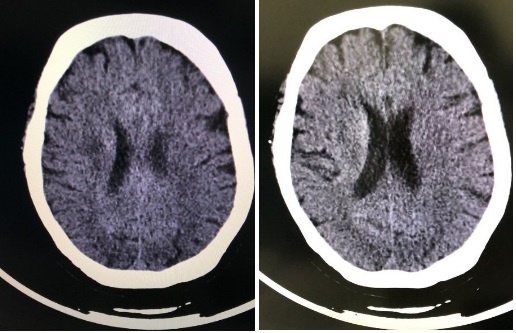

患者女性,71岁,农民,2020年2月6日晚9点左右起夜上厕所时,突发左侧肢体乏力伴口齿不清,摔倒在地,无胸闷、心慌、恶心、呕吐、意识障碍等,后由家人扶至床上观察至次日凌晨3点,症状无明显好转,送至当地医院急诊科,初步诊断为脑卒中,因超过溶栓窗,建议转至上级医院进一步治疗,由急诊120送至江苏省人民医院急诊科就诊,到院后因口罩佩戴不规范,分诊护士指导正确佩戴口罩后送至急诊内科诊间。入院时(2020年2月7日3时45分),测体温37.1℃,呼吸频率18次/min,心率63次/min,血压199/89 mmHg,血氧饱和度99%。既往“高血压”病史8年,口服“苯磺酸氨氯地平片”降压,血压控制在140/80 mmHg左右,“冠心病”病史8年。仔细询问患者家属,患者及其家属发病前2周内居住在家中,无湖北疫区接触史,无新型冠状病毒人员接触史。查体:查体:神清,精神可,口角歪斜,全身皮肤黏膜完整,无皮疹,结膜无充血,口唇红, 双侧扁桃体无肿大,呼吸平稳,双肺呼吸运动对称,双肺底可闻及少量湿啰音,心律不齐,心音强弱不等。神经系统检查:神清,言语欠清,定向力、记忆力、计算力正常,查体合作。颈软无抵抗,双侧额纹对称,双瞳等大等圆,对光反应灵敏,眼球各向运动正常,无明确眼震。左侧鼻唇沟变浅,口角右偏,伸舌左偏。左侧肢体肌张力减低,左上肢肌力Ⅲ级、左下肢肌力Ⅲ级,右侧肢体肌张力正常,右上肢肌力Ⅳ+级、右下肢肌力Ⅳ级。生理反射对称存在,左侧巴氏征阳性。NIHSS 6分。辅助检查:血常规:白细胞4.7×109/L、中性粒细胞3.42×109/L、淋巴细胞计数0.8×109/L、淋巴细胞百分比17%,其余未见明显异常。降钙素原 < 0.1 ng/mL、脑钠肽1 090 pg/mL。心肌标志物、降钙素原、凝血四项及D-二聚体未见明显异常。头颅CT(图 1),胸部CT(图 2)。

| 图 1 右侧放射冠梗死灶 |